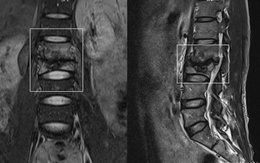

Đau thắt lưng, người đàn ông sững sờ khi phát hiện lao đốt sống

Đau thắt lưng nhiều ngày, người đàn ông 39 tuổi tại Phú Thọ quyết định đi khám. Tại bệnh viện anh sửng sốt khi bác sĩ chẩn đoán hai đốt sống đã bị “ăn mòn”, biến dạng.